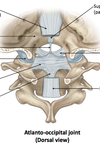

Name the components:

- Name the 3 attachments of the cruciate ligament?

(superior, inferior, transverse)

- What is the purpose of the transverse ligimant?

Superior longitudinal band → basilar part of occipital bone

Inferior longitudinal band → dorsal surface of C2 body

Transverse ligament → small tubercle on the medial aspect of the superior articular facet of C1 (wraps around the dens of C2)

2. Transverse lig. KEEPS DENS FLEXED

- name the attachments of the Anterior atlanto-axial ligament?

- what is it a continuation of?

- Lower edge of ventral arch of C1 ↔ Front of C2 body

- Cranial continuation of anterior longitudinal ligament

- name the attachments of the Posterior atlanto-axial ligament?

- what differentiates it from the posterior longitudinal ligament?

- Lower edge of dorsal arch of C1 ↔ Upper edge of laminae of C2 (arch to arch)

- Distinct from posterior longitudinal ligament (goes fr. Vertebral body to vertebral body)

- name the attachments of the Alar ligament?

- what is its main function?

- Medial tubercles of occipital condyle ↔ Dens of C2

- Resists excessive rotation of head on axial dens